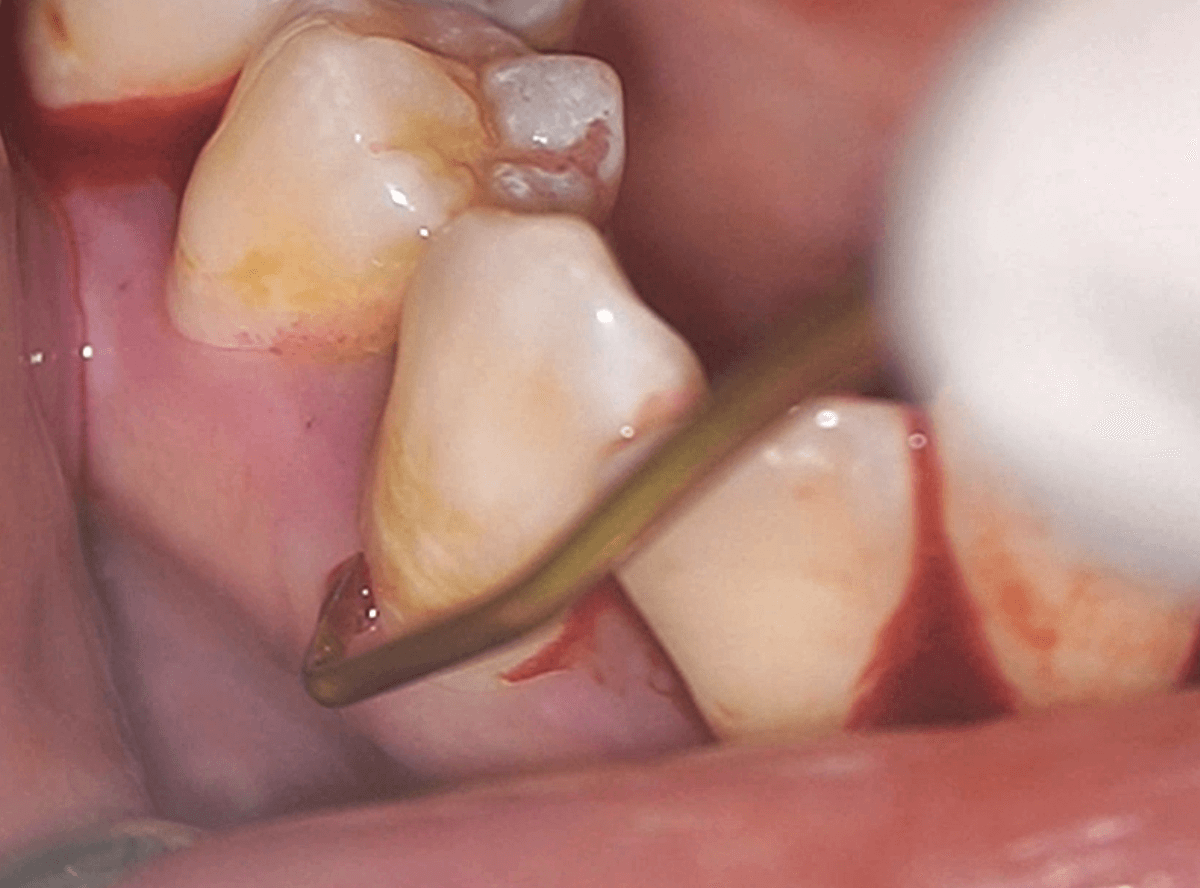

SRP(スケーリング・ルートプレーニング)

歯周病の進行した方を対象に、スケーリング後、さらに歯肉の中に着いた「歯肉縁下歯石」の除去をする処置です。

縁下歯石は、特に歯周病を進行させる原因になります。

縁下歯石は歯茎の中にあるため見えづらく、硬いため、超音波スケーラーに加え、ハンドスケーラーを使って丁寧に除去します。

歯肉の中を触るため、局所麻酔を併用することが多いです。

歯石を除去した歯面は、凹凸のない状態に整え、歯石の再付着を防止します。